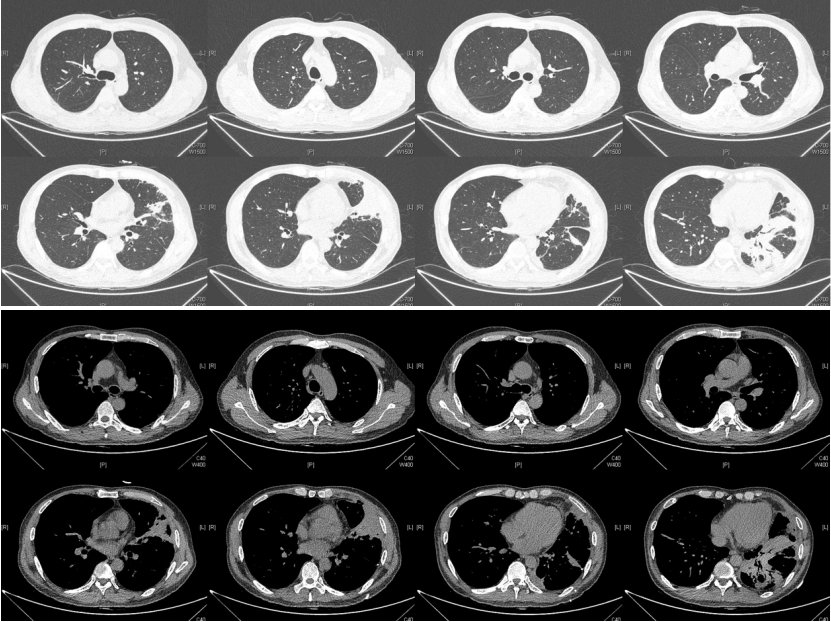

由于厌氧菌培养非常困难,既往我们对厌氧菌的认知仅限于在消化道定植,对其致病机制以及何种情况下致病并不非常清楚。厌氧菌定植于皮肤黏膜,是一种内源性微生物,感染发生率高,可导致严重、致死性感染。由于标本采集和转运的特殊性,使厌氧菌难以分离;加之其培养困难,体外生长慢,所以既往很难识别。厌氧菌在治疗方面存在一定挑战,如往往混合多重感染,且易产生耐药,也会因治疗延迟导致治疗失败。随着近10年来NGS技术的应用和普及,我们对厌氧菌的认识得以提升。常见的致病厌氧菌分为革兰阳性球菌、革兰阴性球菌、革兰阳性非芽孢杆菌、革兰阳性芽孢杆菌以及革兰阴性杆菌(表1)。革兰阳性非芽孢杆菌中可能致病的是放线菌,例如龋齿放线菌参与龋齿的发病过程。革兰阳性芽孢杆菌往往具有致病性,其中产气荚膜杆菌、艰难梭菌/难辨梭状芽孢杆菌、肉毒杆菌/肉毒梭菌、破伤风梭菌/杆菌具有强致病性。革兰阴性杆菌中的拟杆菌属对青霉素类药物具有很强的耐药性,易致青霉素治疗失败。临床中我们与厌氧菌的接触逐渐增多,对其特点也会愈发熟悉,对于临床诊断和治疗也会有所帮助。在NGS报告中通常会将检出的厌氧菌列为“C类”,定义为致病性C类—呼吸道正常微生态菌群,一般不导致感染。但当患者存在误吸风险时,需关注厌氧菌引起肺脓肿的可能。此时就需要针对患者的危险因素、临床表现、影像学、病原学以及气管镜下特点等进行综合分析。微小单胞菌最早是通过培养进行鉴定。瑞士2015—2022年132例病例报告的培养鉴定结果显示,血液中检出微小单胞菌37例(28%),肺内(肺脓肿、脓胸)检出29例(22%),总体病死率较低(5.3%)。国内周华教授团队开展的一项回顾性研究分析了2019年1月至2020年7月经病理活检和mNGS诊断的5例与微小单胞菌相关的慢性肺脓肿患者。患者的平均病程为6.5个月,共同特征是口腔卫生差,有酗酒史,且CT表现为边界不规则的高密度团块状实变影,并且在病灶中间可见液化性坏死,但没有发现气液平面或空腔,所以前期易被误诊为肺癌。下图1是该研究报告中病例3的肺部CT表现。时间点1:首次就诊时,左下叶可见团块状肺不张,伴周围磨玻璃样渗出病变,中心坏死不明显,可见细小空气囊泡影。时间点2:发病8个月时,可见大面积肺实变,增强CT示病灶内有液化坏死和小空洞。时间点3:经过3个月的有效抗厌氧菌治疗,病灶明显缩小,遗留空洞和纤维增殖病灶。图2是病例4的肺部CT表现。时间点1:患者首次就诊时,右上叶可见肿块样肺部实变影。时间点2:发病8个月时增强CT,可见实变明显增大,病灶内出现液化坏死。时间点3:经过3个月的有效治疗,病灶明显缩小,有残留空洞和纤维瘢痕样病变。由于通过影像学鉴别该病与肺癌具有挑战性,所以5例患者都接受了支气管镜检查和CT引导下经皮肺活检。5例患者经组织活检或支气管肺泡灌洗液(BALF)标本mNGS检测到微小单胞菌。病例: 女性, 67岁, 主诉"咳嗽咳痰2个月"。现病史:2个月前,患者家属感染新冠病毒(家属新冠抗原阳性)之后,患者出现咳嗽咳黄脓痰,无痰中带血及痰液拉丝,痰无臭味,无胸闷气短及胸痛,无咽痛咽痒,无鼻塞流涕。6月9日于当地市医院住院,住院期间出现发热,体温最高38.6℃,无寒战,查新冠病毒核酸阳性,予先诺特韦/利托那韦片口服治疗。查胸部CT见左肺上叶软组织影,左肺上叶炎症。诊断肺脓肿,予头孢唑肟联合莫西沙星,治疗后复查胸部CT(6月26日)病灶较6月9日明显吸收好转。6月14日气管镜检査见左肺上叶支气管开口狭窄,见大量脓性痰液堵塞支气管开口(病原学结果家属无法提供)。6月30日办理出院后仍有咳黄脓痰,无发热畏寒,口服止咳化痰药物,未使用抗生素。7月30日复诊胸部CT见左肺上叶异常密度较前增大。8月2日再次于当地市人民医院住院。8月4日气管镜检查: 左肺上叶黏膜肿胀肥厚, 管腔狭窄, 见大量白色干酪样分泌物涌出, 支气管镜不能进入。内科予莫西沙星静滴治疗10天, 外科予莫西沙星联合哌拉西林他唑巴坦静滴9天。复查胸部CT见病灶较前进展, 且右肺出现新发感染病灶。病程中患者饮食可, 睡眠差, 二便正常, 体重减轻5 kg。既往对阿莫西林过敏, 表现为口服阿莫西林后全身皮疹。否认嗜酒史及吸烟史。入院后胸部增强CT可见病灶内液化坏死,同时伴有小的空气囊泡影(图3)。患者有胸痛症状。气管镜检查发现气道内有痰栓或黏液栓阻塞征象(图4)。灌洗液tNGS结果回示:微小单胞菌(序列数2762),巨细胞病毒(序列数171),副流感病毒(序列数79),EB病毒(序列数61)。考虑病毒不会导致气道内如此改变,但由于微小单胞菌属于常见口腔定植菌,此时也不能完全确定微小单胞菌是否为引起感染的主要责任病原体。8月24日起予莫西沙星0.4 g qd ivgtt+哌拉西林他唑巴坦4.5 g q8h ivgtt。经过上述治疗,患者局部病灶有所吸收,但整个肺叶并无明显改善(图5)。气管镜检查仍然发现气道内有较黏稠的黏液栓阻塞气道开口(图6)。治疗经过:气管镜下予以局部冲洗,再次送检tNGS。9月7日结果回示:微小单胞菌(序列数6464),较前明显增多;副流感病毒(序列数998),EB病毒(序列数331)。9月9日起调整治疗方案为美罗培南1 g q8h。9月12日复查患者胸部CT,可见肺通气部分改善,肺组织内实变较前吸收(图7)。第三次气管镜检查仍可见少量痰栓嵌塞在远端支气管开口(图8)。患者此后转入医联体医院继续抗感染治疗。病例2:女性,54岁。主诉:咳嗽咳痰2个月,发热1周。现病史:入院2个月前,患者在西南地区旅游时感冒,出现咳嗽咳痰,白痰为主,量多,无胸痛,无发热,无痰中带血,咳时气短。于河北某诊所间断输液治疗14天(具体不详),期间口服中药治疗,症状未缓解。入院3周前(2023-09-07)就诊于当地县医院,查胸部CT提示右肺炎症,静脉滴注氨曲南、左氧氟沙星、氨溴索治疗1周,症状未缓解。2023年9月14日复查胸部CT显示右肺炎症较前加重,于当地中心医院住院。动脉血气分析:pH 7.43,PaCO2 38.4 mmHg,PaO2 67 mmHg,SaO2 94.2%;血沉90 mm/h;生化:白蛋白35.3 g/L;CRP 82.7 mg/L;血常规:WBC 9.75×109/L,NEU 6.83×109/L,HGB 104 g/L。静脉滴注莫西沙星。入院10天前,行肺穿刺活检,病理回报为少量肺组织及纤维结缔组织,炭末沉积,较多中性白粒细胞、淋巴细胞及浆细胞浸润,伴脓肿形成;肺穿刺mNGS结果回报:微小单孢菌(序列数2650),鲍曼不动杆菌(序列数17),人类疱疹病毒4型(序列数60),人类疱疹病毒7型(序列数5),文氏密螺旋体(序列数4337),解卵磷脂密螺旋体(序列数1121),齿垢密螺旋体(序列数698)。调整抗生素为头孢哌酮舒巴坦2 g q12h。入院1周前,出现发热,体温最高38.5℃,不伴寒战,咳嗽咳痰无加重,无咯血;复查血常规、PCT、CRP均明显增高(未见报告单);复查胸部X线提示右肺炎症范围增大,右侧胸腔积液。更换抗生素为哌拉西林他唑巴坦4.5 g q8h。4天前,支气管镜下见右肺下叶背段支气管略狭窄,黏膜水肿,可见脓性分泌物溢出。BALF革兰染色查见革兰阴性杆菌,抗酸染色、霉菌未见异常,培养未回报。患者体温逐渐降至正常,咳嗽咳痰有所减轻,复查胸部CT提示右肺高密度影,右侧胸腔积液较前增多。为求进一步诊治来我院就诊被收入院。既往甲状腺功能减退病史5年,目前口服优甲乐治疗,监测甲状腺功能指标在正常范围。20年前因宫外孕行手术治疗。2023年10月8日胸部CT示胸膜下斑片状坏死,纵隔窗可见微小空气囊泡影及密度不均匀液化坏死(图9)。治疗:9月28日至10月13日莫西沙星0.4 g qd ivgtt+哌拉西林他唑巴坦钠4.5 g q8h ivgtt。最终患者病灶吸收好转并顺利出院。患者男性,42岁。主因间断咳嗽、咳痰1月余,左侧胸痛、气短2天入院。现病史:入院前1月余(2022-07-19),患者无明显诱因出现咳嗽,咳白痰,痰中有少量鲜红色血丝,左侧胸痛(为钝痛),深吸气后加重,就诊于当地医院。完善肺动脉CTPA:示左上肺动脉舌段分支局部管腔可见线条样低密度充盈缺损,考虑肺栓塞;左肺上叶实性病变伴不均匀强化,性质待定,部分为肺梗死改变可能,纵隔多发稍大淋巴结,性质待定;右肺下叶后基底段可见一不规则实性结节,边缘可见多发毛刺,直径约0.7 cm。当地医院考虑肺栓塞不除外,肺部感染?右肺下叶结节,予莫西沙星抗感染,低分子肝素抗凝,乙酰半胱氨酸化痰。完善CT引导下肺穿刺活检,病理示:肺泡腔扩张伴上皮轻度增生,肺泡间隔纤维组织增生伴散在炎细胞浸润,未见恶性病变。院外规律应用甲磺酸艾多沙班60 mg bid抗凝,先后间断应用左氧氟沙星0.5 g qd、头孢类抗生素(具体药物、剂量不详)抗感染。患者仍有间渐咳黄白痰,量不多,痰中有少量鲜红色血丝;无畏寒、发热、胸痛、夜间阵发性呼吸困难症状,无尿少、双下肢水肿,无口干、咽干,无牙齿成片脱落,无晨僵、关节肿痛,周身无皮疹,无盗汗乏力。2天前(2022-09-16)患者无明显诱因再次出现左侧胸痛,疼痛剧烈,深吸气、咳嗽及改变体位时加重,伴气短,就诊于我院急诊。完善肺动脉CTPA:肺动脉主干及其各叶段分支未见明显充盈缺损,左肺上叶舌段团块影,最大截面约7.6 cm×5.3 cm,边界不清,周围可见晕征;增强扫描不均匀强化,邻近胸膜增厚,性质待定,建议穿刺活检;纵隔及左肺门多发淋巴结显影。血细胞分析:WBC 11.09×109/L,NEU% 80.8%,NEU 8.95×109/L;CRP 54 mg/L,PCT 0.07 ng/ml。患者自发病以来,精神状、食欲及睡眠均一般,大小便正常,体重下降5 kg。2022年9月14日外院胸部增强CT:胸膜下楔形的影像学表现可见少量小气泡囊以及液化坏死病灶(图10)。初始考虑肺部肿瘤及肺栓塞。经过初步抗感染及抗凝治疗,患者病情无缓解,2022年9月27日患者突发胸痛,下肺影像加重并且出现脓胸(图11)。行胸腔穿刺并将脓液送检mNGS,结果回报:牙龈卟啉单胞菌(序列数3)。尽管序列数很低,但考虑是脓肿穿刺结果,因此考虑该菌致病可能。抗厌氧菌治疗:9月16-28日莫西沙星0.4 g qd ivgtt,9月23日-10月12日美罗培南1 g q12h ivgtt,9月28日-10月8日万古霉素1 g q12h ivgtt,10月13-18日莫西沙星0.4 g qd ivgtt+甲硝唑0.5 g tid ivgtt。患者肺脓肿的整体治疗时间约为3个月,病灶逐渐吸收,最终形成一些纤维索条影(图12,图13)。1年后复查病灶基本吸收(图14)。图14 1年后复查胸部CT(2023-08-08)微小单胞菌和卟啉单胞菌这两种厌氧菌在临床中需要引起重视,它们容易引起肺脓肿/脓胸。2024年国内学者Li Yao等在Diagn Microbiol Infect Dis 杂志发表了一篇牙髓卟啉单胞菌感染所致肺脓肿的病例报告,文章也提到在胸水或肺组织活检中,通过mNGS同时检出了微小单胞菌和卟啉单胞菌感染引起的肺脓肿。文章还回顾总结了既往发表的厌氧菌感染引起肺脓肿的病例,2010年报道的是1例脑脓肿患者,2019年报道1例脑炎患者,2022年报道1例脓胸伴呼吸衰竭患者。3例患者预后都比较好,可见厌氧菌亦可导致肺外多部位感染。对于厌氧菌所致肺脓肿的诊断及其引起的脓胸,目前的文献报道仍然较少,我们对它们的认知也有限,因此也提醒大家关注相关疾病的诊断和治疗。我们也已将本研究小组8例微小单胞菌所致肺脓肿的系列病例的研究结果发表(Front Cell Infect Microbiol, 2024, 14: 1416884),可供需要的同行参考。对于厌氧菌感染,我们需要提高警惕。厌氧菌往往在口咽部定植,其引起的脓肿/感染往往多为亚急性或慢性起病。患者通常有发热、胸痛症状,脓肿会逐渐进展。由于厌氧菌与人体本身是一种长期共生的关系,人体对厌氧菌的免疫识别可能处于较低的防御反应状态,所以会形成一个亚急性或慢性的发病过程。通常情况下,因厌氧菌的菌群发生了移位,从卫生条件不好的口腔扩展到相对无菌的肺内,同时开始增殖,由此可能导致感染。因此,对于酗酒以及口腔卫生非常差的人群,我们要重视对其风险因素和病史的排查。患者就诊时可能病情并不重,有胸痛或咯血,很容易误诊为肺部肿瘤,往往在这种情况下进行肺穿刺或气管镜检查,mNGS可以发现较大序列数的厌氧菌。但在mNGS检出厌氧菌后的诊断过程中又容易形成误判——究竟是致病菌,还是定植菌?此时结合患者其他病史和影像学特点(有脓肿/痰栓形成,微小空气气囊泡影),可能提示厌氧菌感染。然而,厌氧菌感染在病原学和影像学诊断方面仍然存在诸多困难,极易漏诊和误诊。微小单胞菌感染患者在气管镜下可以看到典型的脓性分泌物嵌塞气道,导致气道阻塞,也会造成远端气道和肺泡引流障碍。所以,及时处理气道内痰栓,改善引流,可能是使患者获得良好预后的关键。厌氧菌肺脓肿的吸收比较缓慢,抗感染的疗程也比较长,需要在后期诊疗过程中密切随访和观察患者对治疗的反应以及耐药等问题,及时调整治疗方案,适当延长疗程。